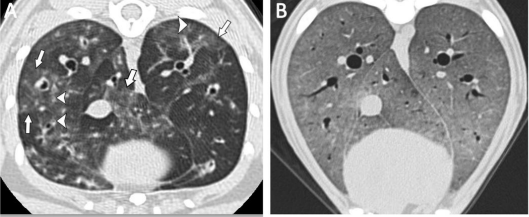

O aumento da densidade pulmonar pode surgir devido a diferentes razões: um acréscimo no tecido pulmonar, muitas vezes causado pelo aumento no número de células, sejam elas inflamatórias, estruturais, tumorais ou infecciosas; um aumento na quantidade de sangue nos vasos; e uma redução no volume de ar nos alvéolos, seja por expiração, por hipoinflação decorrente de condições como obesidade ou distúrbios da cavidade pleural, ou ainda por atelectasia, que é a redução ou colapso total do tecido pulmonar. Os principais padrões que indicam um aumento na atenuação do tecido pulmonar são o ground glass opacity (GGO) (figura 1), a consolidação e uma atenuação que supera a dos tecidos moles (figura 1). O GGO se refere ao aumento da atenuação onde ainda é possível discernir as paredes e os vasos brônquicos. Ele se diferencia da consolidação, onde ocorre a perda das paredes brônquicas e das marcações vasculares, resultando em opacidade completa (MASSEAU e REINERO, 2019).

Figura 1: (A) Gato com asma, as setas indicam áreas multifocais irregulares de opacificação. (B) Cão com pneumonia, demonstrando GGO difuso.

Fonte: Masseau e Reineroa, 2019